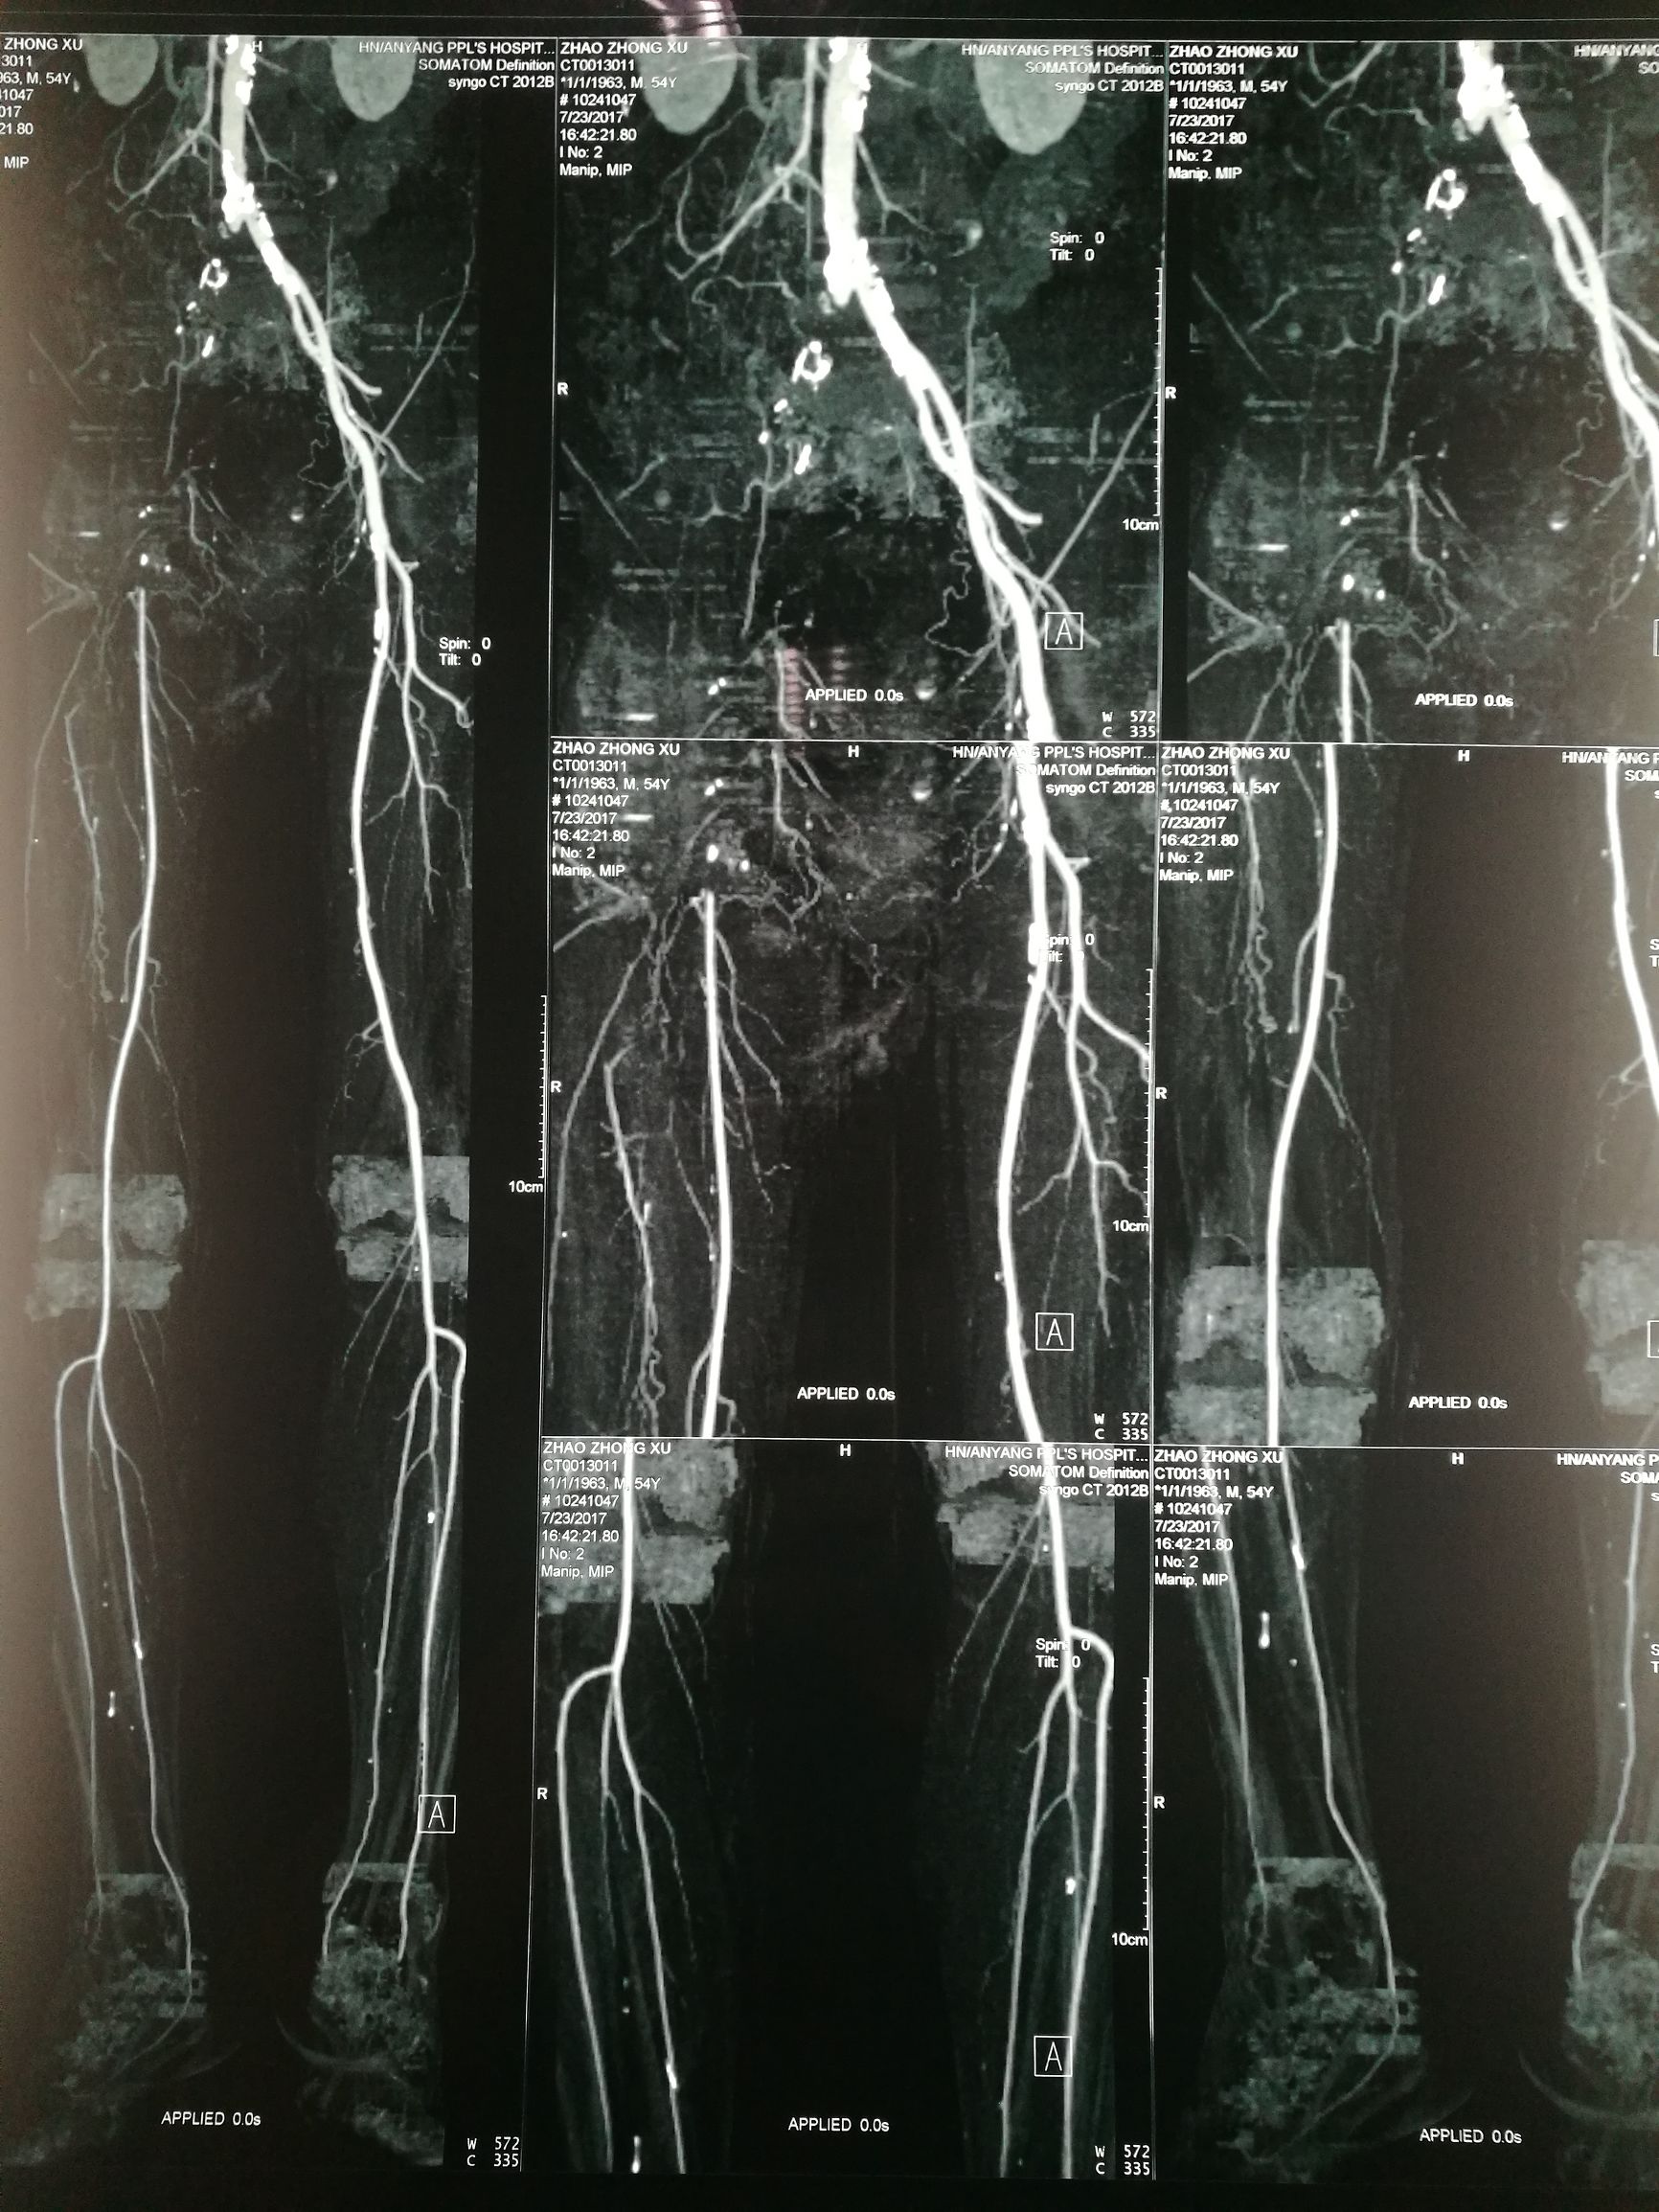

54岁男性,右足疼痛半月余。患者半月前无明显诱因突发右下肢疼痛,行走后加重,休息减轻。超声提示腹主动脉左髂动脉多发狭窄闭塞,右髂动静脉闭塞。CTA

入院后,结合病史,考虑有血栓形成的可能性,行全身静脉溶栓,一周后复查CT,右侧髂总动脉出现一段管腔

对比正常解剖模式图,我们可以发现:右侧髂总髂内髂外股总动脉未显影,股深动脉未显影,右侧股浅动脉起始段未见显影,考虑有血栓闭塞的可能。

术前经讨论,考虑股深动脉的重要性,决定开刀取栓基础上对残余狭窄介入治疗。